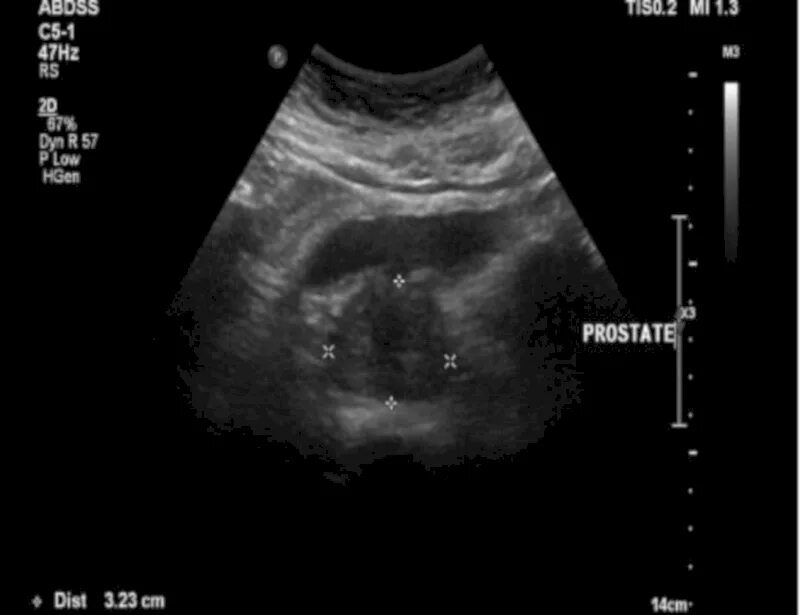

Трансабдоминальное узи